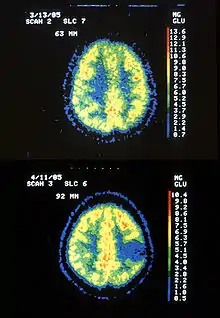

| Two PET images—the upper of which shows a normal brain and the lower shows astrocytoma | |

Astrocytoma is a type of brain tumor. Astrocytomas (also astrocytomata) originate from a specific kind of star-shaped glial cell in the cerebrum called an astrocyte. This type of tumor does not usually spread outside the brain and spinal cord and it does not usually affect other organs. After glioblastomas, astrocytomas are the second most common glioma and can occur in most parts of the brain and occasionally in the spinal cord.[1]